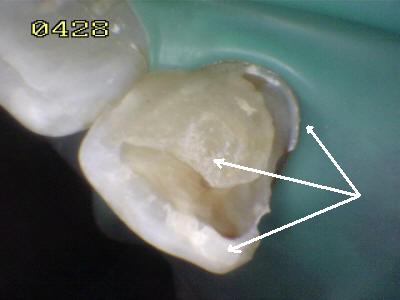

Cementado con la goma dique.  Observe los excesos de cemento de resina de curado dual (flechas blancas)